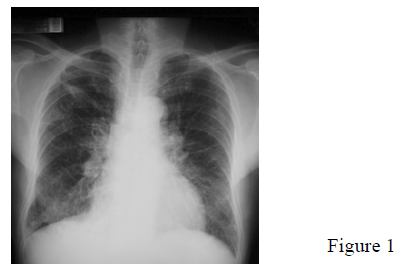

In mid 2004, he started to have productive cough with mucoid sputum. He also had mild exertional dyspnoea but no haemoptysis or chest pain. Constitutional symptoms were also absent. CXR showed new BLZ fine reticulonodular shadows (Fig.1). Sputum examination for AFB, cytology and pyogenic organisms were all negative.